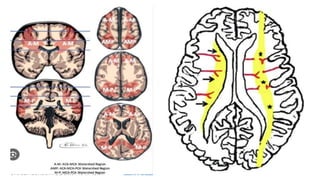

• MRI :- Best imaging modality for determining the presence , severity & distribution of irreversible HI brain

injury.

1. Diffusion – weighted imaging (DWI) – Early DWI –usually show restricted diffusion in areas affected by

hypoxic- ischemia

At 7 to 10 days – pseudonormalisation of diffusion

After 7 to 10 days - diffusion usually increased in areas of affected areas

• MRI - useful tool in the determination of prognosis.

• Injuries to the basal ganglia or thalamus have an unfavourable neurologic outcome

when compared with infants with a white matter predominant pattern of injury.

• Abnormal signals in the PLIC have also been associated with poor neurologic

outcome at 2 years of age.

BRAIN IMAGING MODALITIES:- •CRANIAL SONOGRAPHY :- can demonstrate edema as loss of gray-white differentiation and small ventricles when severe but is generally insensitive for detection of HI injury. • CT :- used to detect cerebral edema , hemorrhage and eventually HI brain injury. • MRI :- Best imaging modality for determining the presence , severity & distribution of irreversible HI brain injury. 1. Diffusion – weighted imaging (DWI) – Early DWI –usually show restricted diffusion in areas affected by hypoxic- ischemia At 7 to 10 days – pseudonormalisation of diffusion After 7 to 10 days - diffusion usually increased in areas of affected areas 2. Proton Magnetic Resonance spectroscopy(MRS) 3. Susceptibility – weighted imaging 4.Magnetic Resonance Angiography or Venography

• MRI -useful tool in the determination of prognosis. • Injuries to the basal ganglia or thalamus have an unfavourable neurologic outcome when compared with infants with a white matter predominant pattern of injury. • Abnormal signals in the PLIC have also been associated with poor neurologic outcome at 2 years of age. • Echocardiography An echocardiogram to evaluate the cardiac contractility and ejection fraction. Neonates with HIE receiving therapeutic hypothermia may experience a reduction in cardiac output and descending aorta blood flow.